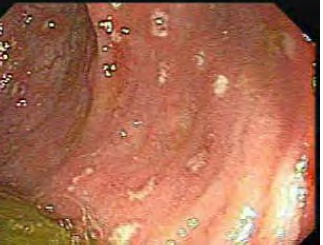

Na endoscopia digestiva baixa, observam-se as membranas.